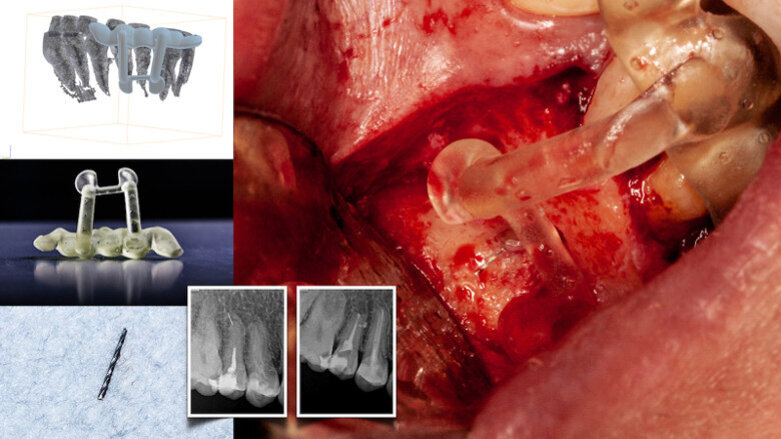

The advent of cone beam computed tomography (CBCT—DICOM files) and 3D printing has transformed pretreatment planning. DICOM files are converted into stereolithic files, which are used to create static navigation stents (CAD/CAM-fabricated). The stents direct the access cavity preparation and microsurgical orientation, thus avoiding removal of unnecessary tooth and bone structure (Figs. 1a & b).

Stereolithic stents (static navigation) require a medium field of view CBCT scan. Polyvinylsiloxane impressions of the arch to be treated are poured and a digital 3D scan of the stone model merged with the patient’s DICOM files. The use of an intra-oral scanner is preferable.

The heightened level of accuracy of TaP technology enhances the facility of treatment for restricted access cavity preparation and minimises the size of cortical window osteotomies (high-speed; Piezotome, ACTEON). Ultrasonic tips used for root end retro-preparation can also be tracked by dynamic navigation software.

The first stage of TaP workflow is the importation of the patient’s CBCT data set (as DICOM file) into the dynamic navigation planning software to reveal the dentition. The screen shows the streaming video, panoramic view, target view, depth indicator, and buccolingual and mesiodistal section views (Fig. 3). The access point of entry, the axis orientation/angulation and the depth of the access cavity are planned. For microsurgical procedures, the Piezotome pathway is based on the dimensions of the osseous pathology surrounding the root apex (Figs. 4a–c). The planning stage can be done at any time prior to the procedure, provided the CBCT scan is consistent with the current dentate condition. As a preliminary step prior to the trace registration, three to six trace starting points (landmarks) are chosen and marked on visible and accessible teeth. When the computer mouse is positioned over the 3D model, a 2D cross-sectional view appears. The red crosshair sticks to the landmark, its centre on the surface (Fig. 5). The software advises the clinician if it suspects that the landmark is in an incorrect position.

The Jaw-Tracker (mandible or maxilla) or Head-Tracker (maxilla) is securely fastened to the jaw to be treated (Fig. 6). It should be noted that the Jaw-Tracker can be positioned at a distance from the rubber dam, unlike a Jaw-Tracker attached to a fiducial stent, which is more positionally restricted. Once the three landmarks have been determined, the optical tracking sensor tracks the Tracer- Tag/ Tracer- Tool as it is brushed around the landmarks on the facial, lingual and occlusal surfaces in a manner similar to applying etching or bonding solutions. The software shows the number of points contacted as a percentage (Fig. 7).